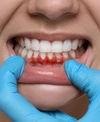

نزيف اللثة

أمراض الأسنان واللثة